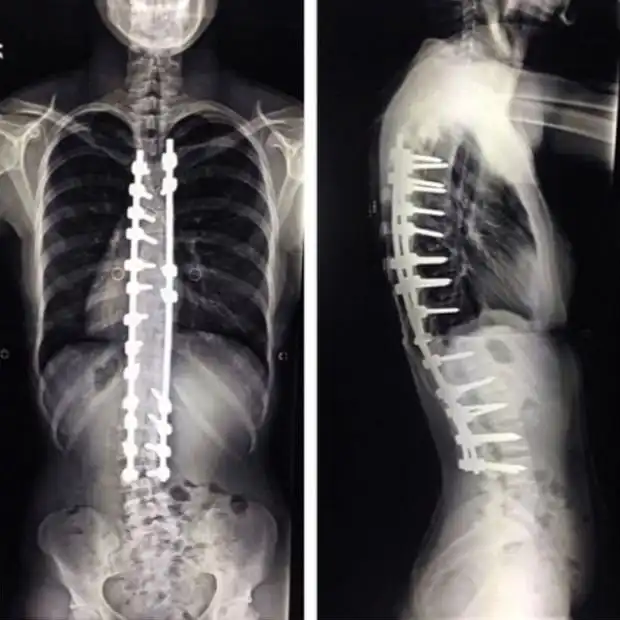

Из-за сколиоза позвоночник может принять совершенно дикую форму, и в таких случаях не обойтись без спондилодеза. Операция довольно серьезная, а ее последствия весьма болезненны. Пациенты приходят в себя в течение нескольких месяцев, сидя все это время на обезболивающих. Эта девушка сумела все это пережить, и теперь она живет полноценной жизнью, хотя некий дискомфорт чувствует до сих пор.